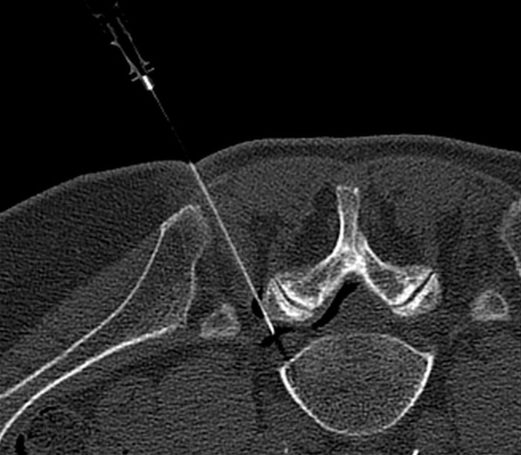

Facet Injections

Facet joint injections are a minimally invasive way to relieve pain and inflammation in the small joints of your spine. Using CT guidance, we can precisely deliver medication directly to the affected facet joint, helping reduce discomfort from arthritis, injury, or chronic back and neck pain. Most patients experience improved mobility and pain relief after a short, outpatient procedure.

CT imaging provides a 360-degree, cross-sectional view of your spine and anatomy. We can see the needle tip in real-time, ensuring it is placed within millimeters of the target nerve or joint.

Because CT scans visualize soft tissues and blood vessels—not just bone—we can navigate around sensitive structures that are invisible on standard X-rays. This significantly reduces the risk of complications.

For patients with scoliosis, arthritis, or previous spinal surgery (including screws and rods), standard landmarks can be obscured. CT guidance allows us to navigate complex anatomy with ease, ensuring successful treatment even in difficult cases.

Because we can place the medication precisely at the source of inflammation, we often achieve better pain relief without the need for excessive medication spread.